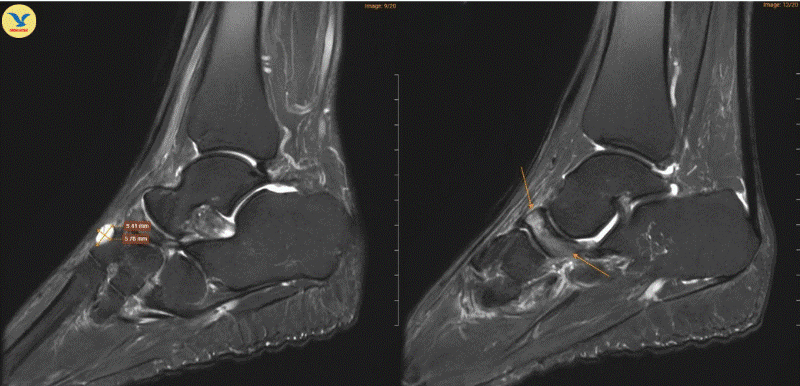

| Hình ảnh chụp MRI cho thấy những dấu hiệu đặc trưng của Hội chứng Mueller-Weiss ở chân phải |

Tại MEDLATEC , bác sĩ đã chỉ định chụp Cộng hưởng từ (MRI) để tìm kiếm những tổn thương sâu trong cấu trúc xương. Trên lát cắt Sagittal T1W, hình ảnh cho thấy xương ghe bị xẹp và biến dạng điển hình hình dấu phẩy, kèm theo tình trạng đặc xương dưới sụn. Trên chuỗi xung T2W FS, ghi nhận tình trạng phù tủy xương ghe rõ rệt.